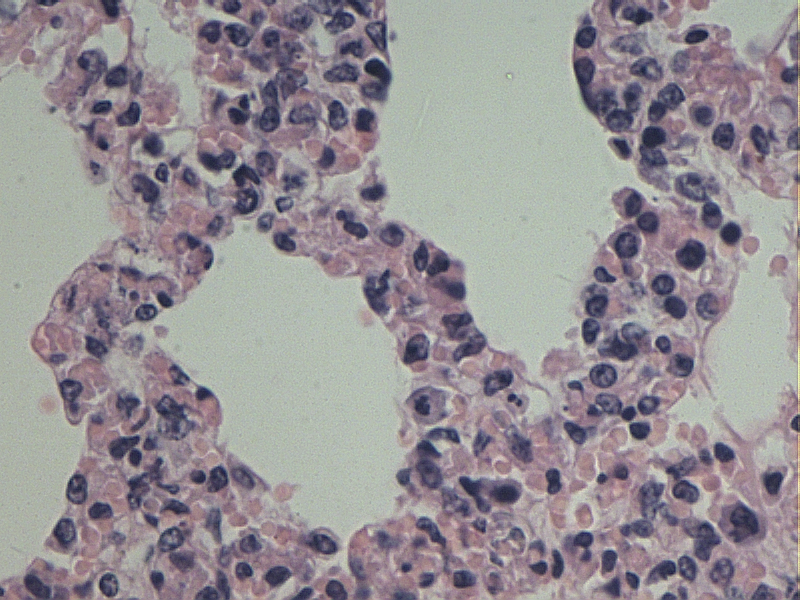

间质性肺炎

支气管周围大量炎性细胞浸润

肺泡隔增厚